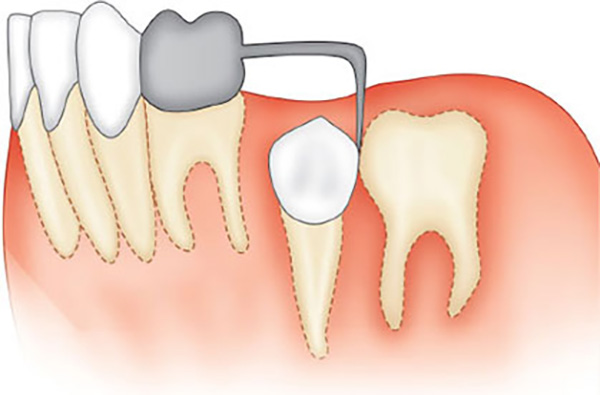

- Band & Loop Appliance – A metal band is fitted around a molar, and a loop of wire is attached to hold space where a tooth was lost. It prevents surrounding teeth from tipping into the gap. Once the permanent tooth’s root is two-thirds formed and begins to erupt, the device is removed.